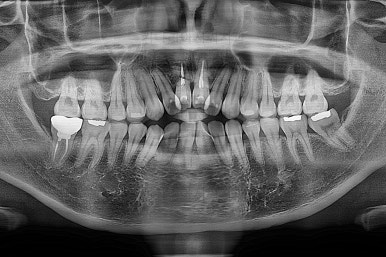

오늘 부산개방교합 키다리아저씨치과에서 소개해 드릴 환자분은 앞니가 부러져 임플란트를 해야 하는 환자분으로 개방교합(오픈바이트, open bite)과 돌출입을 함께 개선했던 분입니다.

1. 초진

부산개방교합 키다리아저씨치과에 처음 내원 시 입안의 모습입니다.

전반적으로 치열이 삐뚤고요.

앞니쪽이 다물어지지 않는 개방교합(오픈바이트, open bite) 을 보였습니다.

어금니 맞물림을 보면 앵글씨 2급 부정교합 양상이어서 위아랫니가 모두 1대1로 부딪히고 있는 상태였습니다.